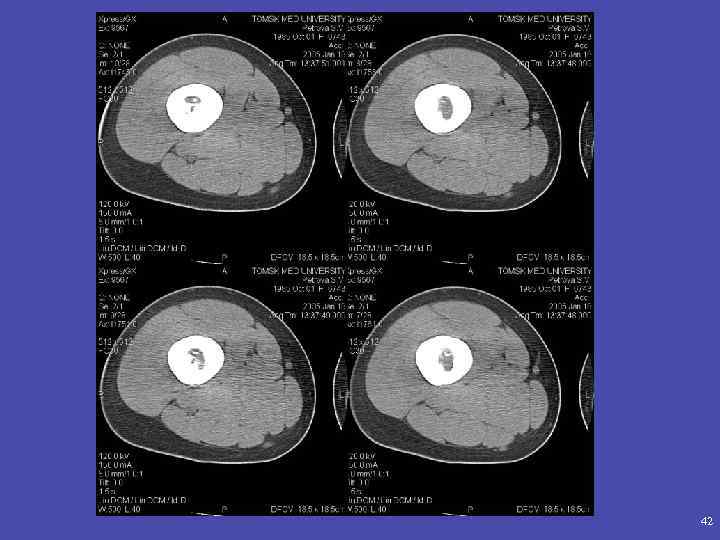

КОМПЬЮТЕРНАЯ ТОМОГРАФИЯ • Выявление деструкции (опухоли, воспаление) Спикулообразный периостит левой подвздошной кости, мягкотканый компонент опухоли.

• Диагностика распространенности опухолевого процесса